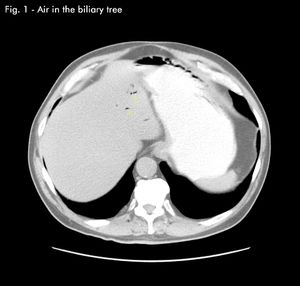

Gallstone IleusByDavid Jacobs, MD,Ken Nalaboff, MDJune 9th 2011 A 70-year-old patient recently presented to an emergency department with a history of abdominal distention, pain and brownish emesis.